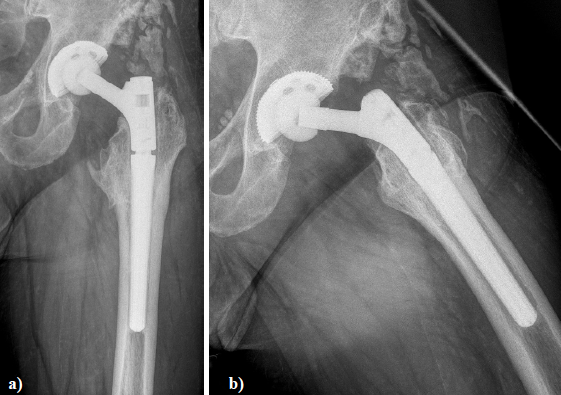

Figure 4. X - ray of the left hip in 2 planes: ap view a. and lateral; b view shows status after revision of THA using a long varus neck and a cementless cup.

Figure 7. X - ray of the left hip in 2 planes: ap view a. and lateral; b. view shows revision arthroplasty of the hip using a long bended MRP Titan revision stem with long neck and extension sleeve.